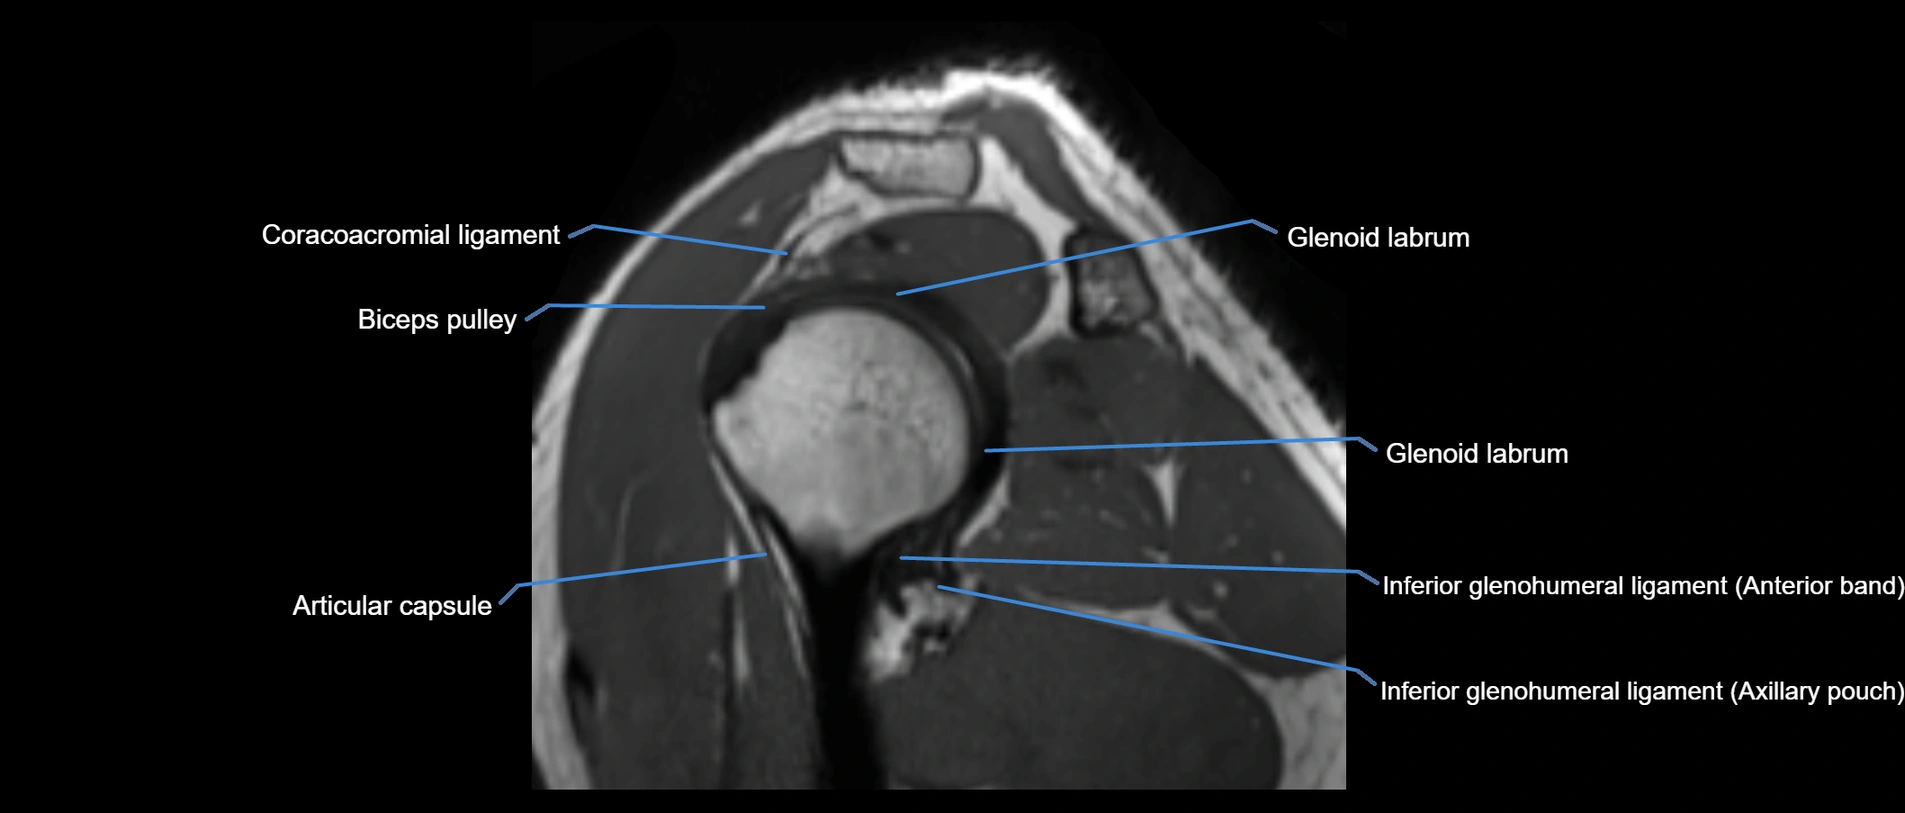

MRI images

image